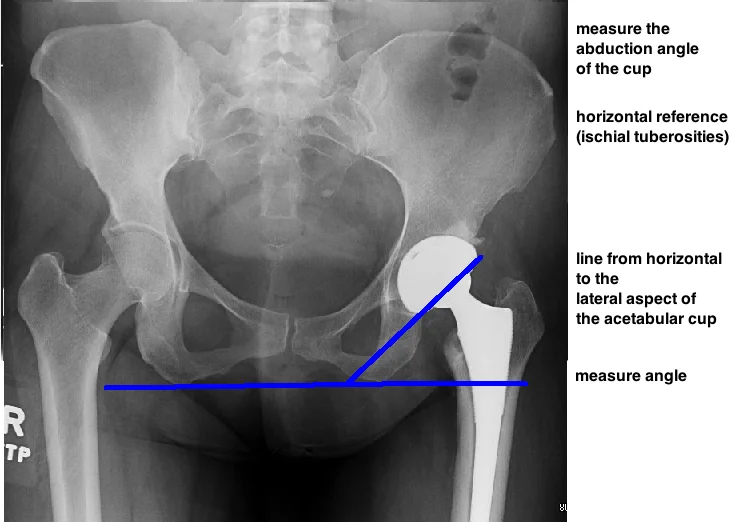

POST-OP EVALUATION

START BY EVALUATING CUP PLACEMENT